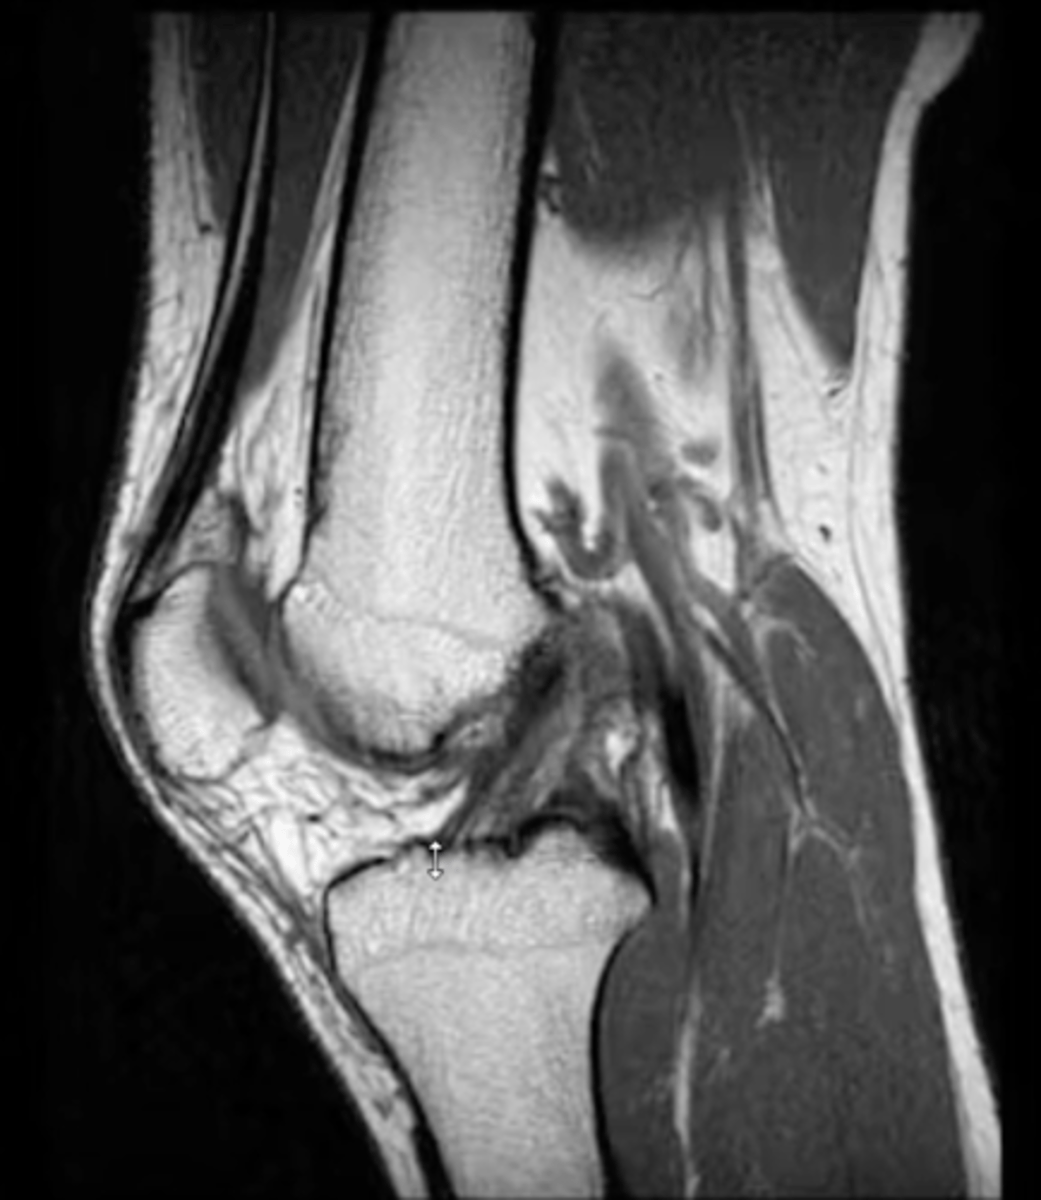

ACL (always goes inferior --> superior in a posterior direction)

Which ligament can you see in this sagittal view?

A = healthy ACL running inferior & anterior to superior & posterior

B = fully torn ACL (since the ligament is laying down flat on the tibia, we know that it is a full tear...if it were a partial tear, it would just appear wavy)

What is the difference between image a and b?

Complete tear of the ACL (right down the middle)

Define the pathology.

Complete tear of the ACL

Tear of the ACL